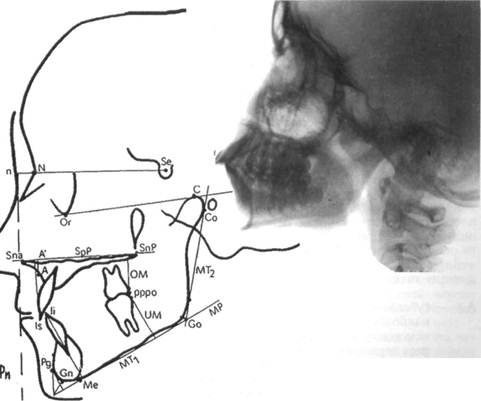

Телерентгенография. Этот метод рентгенологического исследования применяют для изучения строения лицевого скелета, его роста, уточнения диагноза и прогноза орто-донтического лечения, а также для выявления изменений, происходящих в процессе лечения. Телерентгенографию проводят в боковой и прямой проекциях с расстояния 1,5 м. Голову обследуемого фиксируют с помощью цефалостата различных конструкций, применение которых обеспечивает получение идентичных снимков (рис. 13.28).

челюстной системы в трансверсаль-ном направлении, в боковой проекции — в сагиттальном и трансвер-сальном направлениях. На ТРГ видны кости лицевого и мозгового черепа и контуры мягких тканей, что дает возможность изучить их взаимоотношения (рис. 13.29).

Для расшифровки ТРГ снимок помещают на экран негатоскопа, к

| Рис. 13.28. Телерентгенограмма головы, выполненная в боковой проекции. |

Рис. 13.29. Скопированная телерентгенограмма головы.

нему прикрепляют кальку, на которую переносят изображение.

ТРГ по методу Шварца позволяет наиболее полно изучить размер и положение челюстных костей. Пользуясь этим методом, можно провести краниометрические, гна-тометрические и профилометриче-ские измерения. С помощью краниометрии определяют: 1) расположение челюстей в сагиттальном и вертикальном направлениях по отношению к плоскости передней части основания черепа; 2) расположение ВНЧС по отношению к плоскости передней части основания черепа; 3) длину передней части основания черепной ямки.

Для анализа ТРГ используют следующие точки плоскости:

А — субспинальную точку Downs, наиболее глубокую на переднем контуре апикального базиса верхней челюсти;

В — супраментальную точку

Downs, наиболее дистально расположенную на переднем

контуре апикального базиса нижней челюсти;

Se — на середине входа в турецкое седло;

N — на передневерхнем крае но-солобного шва в сагиттальной плоскости;

Ог — наиболее низко расположенную точку нижнего края орбиты;

Go — точку угла нижней челюсти в месте пересечения его с биссектрисой угла, образованного касательными по нижнему краю тела и заднему краю ветви нижней челюсти;

С — самую верхнюю точку на контуре головки нижней челюсти;

Me — наиболее выступающую точку нижнего контура подбородочного отдела;

N — точку на коже, образующуюся при пересечении с продолжением линии N—Se;

Sna — переднюю носовую ость;

Snp — заднюю носовую ость;

Pg — самую переднюю точку подбородочного выступа;

NSe — плоскость переднего отдела основания черепа (ее проводят через точки N и Se);

SpP — плоскость основания верхней челюсти (проходит через точки Sna и Snp);

Рп — носовая вертикаль, которую проводят перпендикулярно к плоскости NSe через кожную точку п;

MP — плоскость основания нижней челюсти.

На ТРГ отделяют краниальную часть черепа от гнатической плоскости верхней челюсти (SpP).

Варианты расположения челюстей определяют по лицевому, инклина-ционному углу и углу горизонтали:

1) лицевой угол F образуется при

пересечении линий N—Se и N—А (внутренний нижний угол). Его величина характеризует расположение верхней челюсти по отношению к основанию черепа в сагиттальном направлении. Угол меньше нормы характерен для ретрогнатии, больше нормы — для прогнатии; если он находится в пределах нормы, говорят о нормогнатии;

2) угол горизонтали Н образуется при пересечении линии Н (горизонтальная линия) и Рп (внутренний верхний угол) и определяет положение суставной головки нижней челюсти по отношению к основанию черепа, что влияет на форму профиля лица;

3) инклинационный угол J образуется при пересечении линий Рп и SpP (внутренний верхний угол). Если угол J больше средней величины, то челюсти наклонены вперед, что Шварц назвал антеинкли-нацией. Если угол меньше средней величины, то челюсти отклонены назад. Такое положение челюстей называется ретроинклинацией.

Гнатометрический метод (по Шварцу) позволяет:

• определить аномалию, развившуюся в результате несоответствия размеров челюстей (длины тела челюсти, высоты ветвей нижней челюсти), аномалии положения зубов и формы альвеолярного отростка;

• выявить влияние размеров и положения челюсти, а также аномалии зубов на форму профиля лица;

• определить индивидуальную форму длины тела челюстей и отклонения в размерах.

Наиболее важные параметры гна-тометрии:

1) базальный угол В — угол наклона основания челюстей друг к другу (SpP — MP), характеризующий вертикальное положение челюстей;

2) длину тела нижней челюсти МТ измеряют по плоскости MP от проекции точки Pg на MP до точки пересечения ее с касательной к ветви нижней челюсти;

3) высоту ветвей МТ измеряют по касательной к заднему краю ветви от точки пересечения с плоскостью MP до проекции точки С на касательной;

4) нижнечелюстной угол G измеряют между линиями МТ] и МТ2, т.е. между касательными к нижнему краю нижней челюсти и задней поверхности ее ветвей;

5) длину верхней челюсти измеряют от точки пересечения перпендикуляра, опущенного из точки А на SpP (точка А'), до точки Sn.

Средние индивидуальные нормативы по Шварцу:

1) длина тела нижней челюсти при ее нормальном развитии равна длине основания передней черепной ямки (расстояние N — Se) плюс 3 мм;

2) длина верхней челюсти по отношению к длине переднего отдела основания черепа составляет 7:10;

3) длина тела нижней челюсти соотносится с длиной ее ветвей как 7:5.